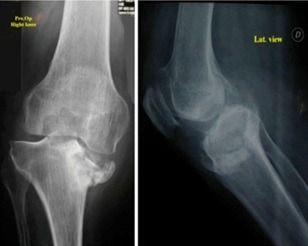

Ακτινογραφίες: Ο ακτινολογικός έλεγχος περιλαμβάνει και τα δύο γόνατα σε προσθιοπίσθιες και πλάγιες λήψεις. Ο έλεγχος γίνεται με τον ασθενή όρθιο έτσι ώστε να φορτίζει με το βάρος του τις αρθρώσεις του γόνατος.

Oι ακτινογραφίες αρχικά είναι σε θέση να μας δώσουν πληροφορίες για ασύμμετρη φόρτιση ή για πιθανές παραμορφώσεις (ραιβότητα, βλαισότητα). Στη συνέχεια ελέγχονται για στένωση του μεσάρθριου χώρου μεταξύ των οστών του μηρού και της κνήμης, σκλήρυνση του υποχόνδριου οστού και δημιουργία νέου οστού στις παρυφές της άρθρωσης (οστεόφυτα).